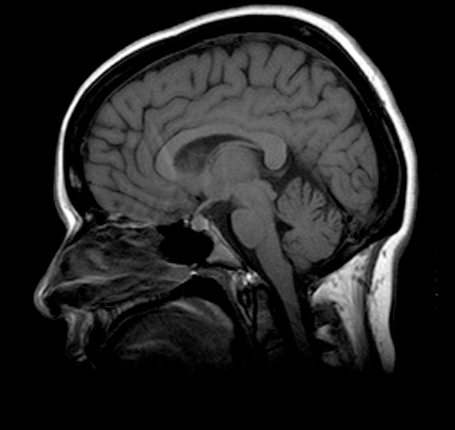

Cerebellum

Cerebral Hemisphere

Diencephalon

Medulla Oblongata

Midbrain

Pons

Straight Sinus

Superior Sagittal Sinus